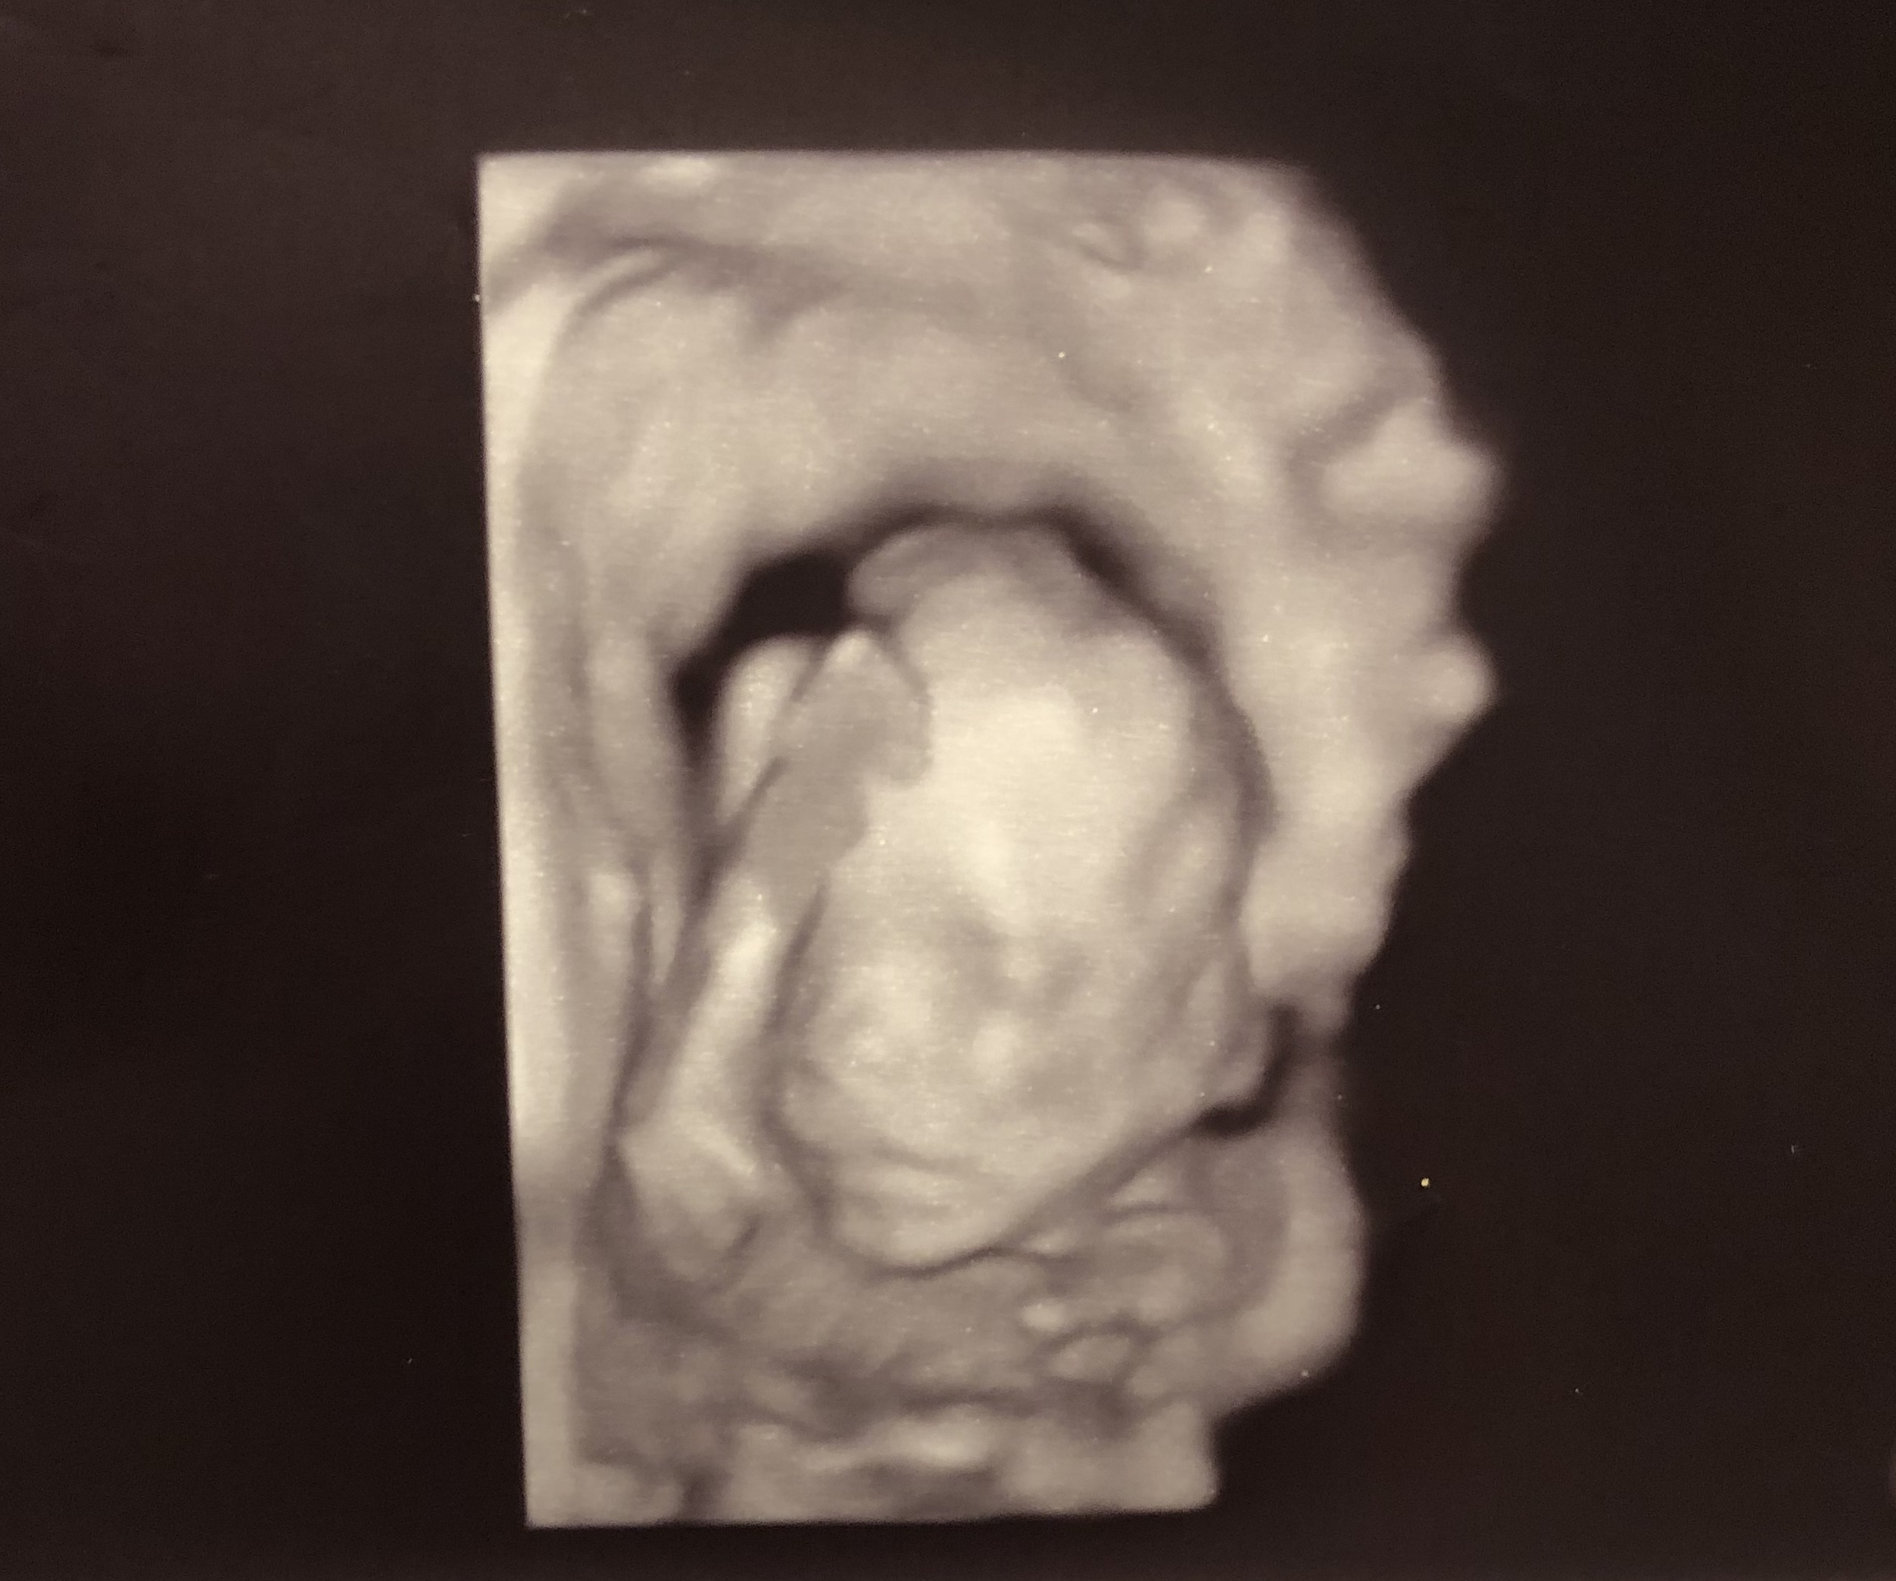

We had our anatomy scan this morning. Turns out baby number three is a boy! Couldn’t be more excited! We got so many great pics but I love this one. It looks a little creepy but when she was trying to get this picture the baby kept opening his mouth and sticking his little tongue out at us. You can even see his tongue in the pic. It was so cute and funny. I already love him so much!!